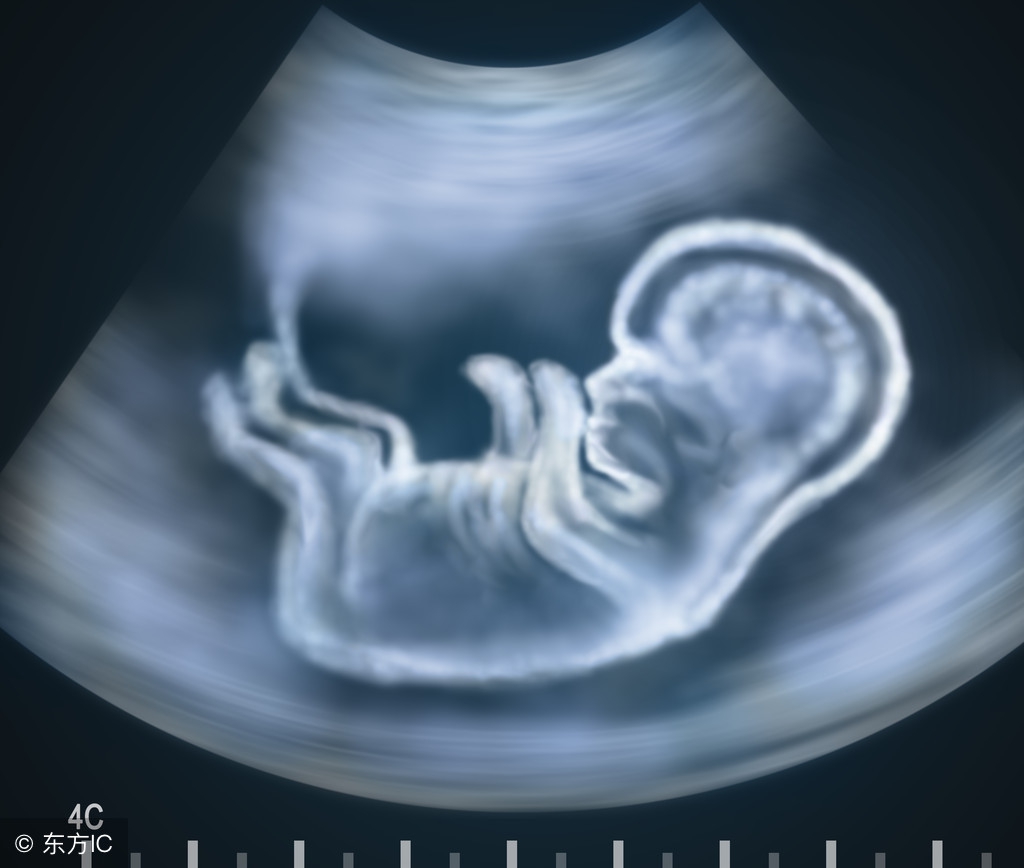

宝宝12周了

胎儿12周

胎宝宝状况:怀孕第12周的时候胎儿身长可达到6.5厘米,现在宝宝已经初具人形,宝宝的成长速度在本周越发惊人。他的一些骨胳开始变硬,手指和脚趾已经分开,他可能很快就能够握紧和打开小拳头了。在本周胎儿维持生命的器官已经开始工作,如肝脏开始分泌胆汁,肾脏分泌尿液到膀胱。